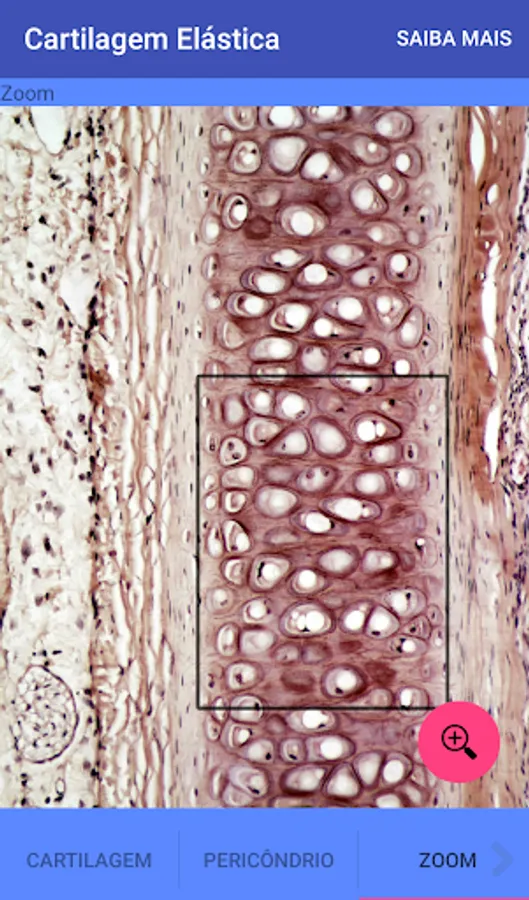

Elastic Cartilage